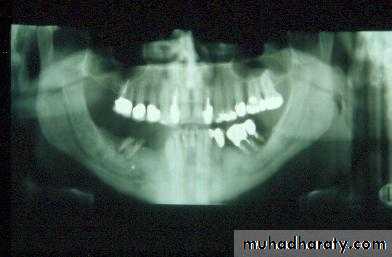

a. Extractions for caries, periodontal disease, infection, etc.

a. Extractions…flap, bone removal, section

a. Extractions and alveolar osteotomy …

removal of proclined incisors andosteotomy of labial plate of bone